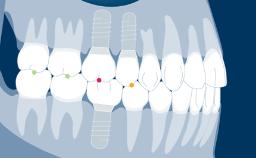

An implant abutment is the part or component that serves as support and/or retention for a dental prosthesis. The selection of the implant abutment for each individual patient case is therefore an important part of the implant-prosthodontic treatment phase. In this module, we will discuss the function of implant abutments, different implant abutment types, different abutment materials and how to select an abutment based on a prosthodontically driven process.

- select abutments based on prosthodontic indications and planning